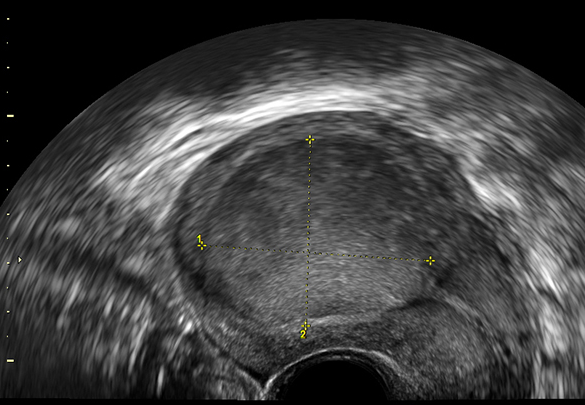

DiagnosticDiagnosticul se poate stabili cu ocazia examinării ginecologice când se poate palpa un uter mărit de volum cu contur neted, regulat în vazul nodulilor intracavitari sau prin examinări imagistice, cea mai rapid accesibilă fiind ecografia.

Pentru a diferenția un leiomiom intracavitar de un polip endometrial poate fi folosită examinarea Doppler color unde, nodulii fibromatoși au un model vascular caracteristic- vascularizație marginală din care doar câteva vase pătrund în centrul tumorii. Tot cu ocazia examinării ecografice se poate stabili modul în care nodulii intracavitari sunt atașați la peretele uterin. Aceștia pot prezenta un pedicul subțiere de atașare sau pot avea bază largă de implantare și pot pătrunde în grosimea peretelui uterin. Nodulii intracavitari pediculați pot produce simptome precum crampe abdominale sau durere acută pe măsură ce aceștia pot descinde prin canalul cervical.